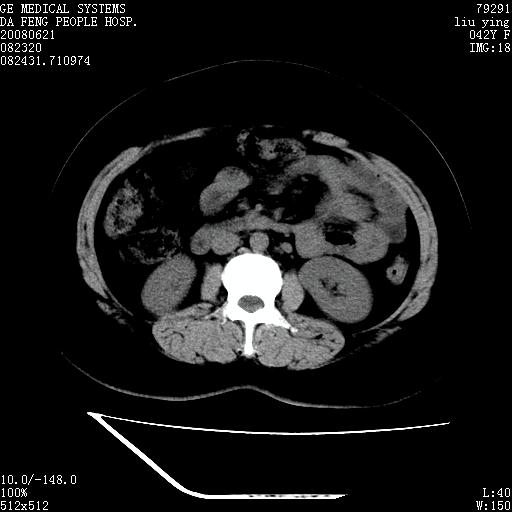

标题: CT14225:女性46岁。当地B超示肝内占位,来我院作CT检查。请 [打印本页]

标题: CT14225:女性46岁。当地B超示肝内占位,来我院作CT检查。请

速升速降,支持肝癌.脾体积增大,形态欠规整,请询问病史是否做过脾动脉栓塞.

速升速降,支持肝癌可能。

右叶肝癌灶;慢性胆囊炎,不除外占位;;副脾可能性

快进快出,符合肝癌表现-----------

肝内结节强化特点符合原发性肝癌表现,脾脏改变考虑为增大及先天发育所致。

动脉期病原灶明显强化高于肝密度且中央有无强化区,静脉期强化程度下降明显,延迟低于肝密度,考虑肝腺瘤可能性大,

肝内结节强化特点:快进快出符合原发性肝癌表现

此患者虽然符合快进的特点,却不符合快出的特点,因为门脉期几乎是等密度,不符合肝癌的增强表现,所以我考虑肝局灶性结节增生可能性大